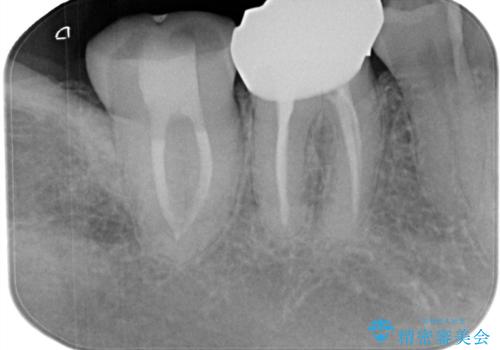

- 冷たいもので長引く痛みがあることを主訴に来院されました。

抜髄を行い、オールセラミッククラウンにて修復を行いました。

根管充填はバイオセラミックシーラーを使用しています。